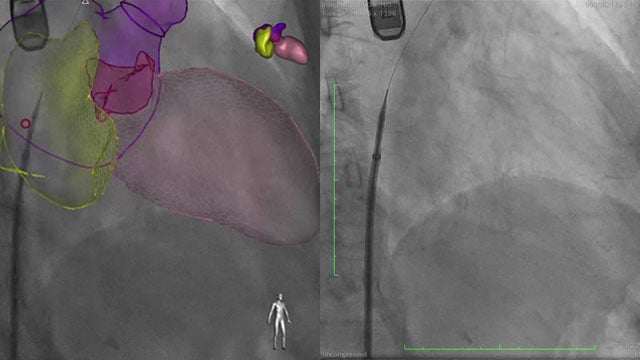

A simple maneuver to track the wire during a transseptal mitral valve-in-valve procedure

05 Nov 2025

Advancing a transcatheter heart valve through the septostomy can be tricky, with the wire sometimes prolapsing into the left atrium.

This step-by-step tutorial demonstrates a simple yet effective maneuver that allows smooth, controlled navigation from the right atrium to the mitral position, ensuring precise valve deployment.